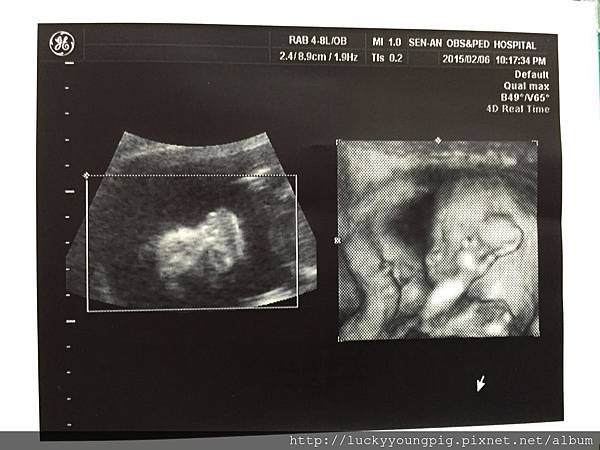

因不是很確定寶貝的姓別 請醫生看一下

醫生說寶貝縮成一團 嗯~等等再看

最後寶貝是男生是女生呢?

醫生說 嗯~應該是女生

醫生又換個角度照 說百分之百是女生

因為這邊有三個點 嗯~大妹與媽咪我真的看不出來啦 +.+